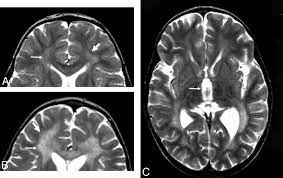

بر اساس این گزارش، این درمان باید در ماه های ابتدایی تولد و پیش از پیشرفت زیاد بیماری انجام شود. در کشور انگلیس در هر سال تنها حدود پنج نوزاد با اختلال MLD متولد میشوند. این اختلال از فقدان یک آنزیم موسوم به Arylsulfatase-A ناشی میشود. فقدان این آنزیم یک ماده موسوم به سولفاتید (sulphatides) تجمیع میشود و در نهایت برخی مواد محافظتی سیستم عصبی را نابود میکند.

در نتیجه عصبهای درون مغز و عصبهای حاشیهای درست عمل نمیکنند و این امر موجب نشانههایی از قبیل ضعف عضلانی، کاهش بینایی و شنوایی، دشواری در راه رفتن، از دست دادن قدرت تکلم، افول شناختی و همچنین تشنج میشود.